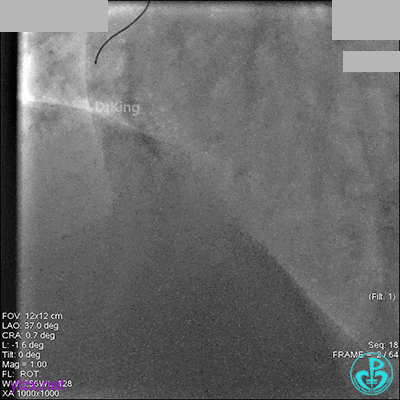

1周后再次上台,右冠脉3级血流,3段局限性严重狭窄,内膜模糊,应该是上次操作夹层遗留下的血肿。

先处理前降支开口严重狭窄并顺利植入前降支到左主干支架。